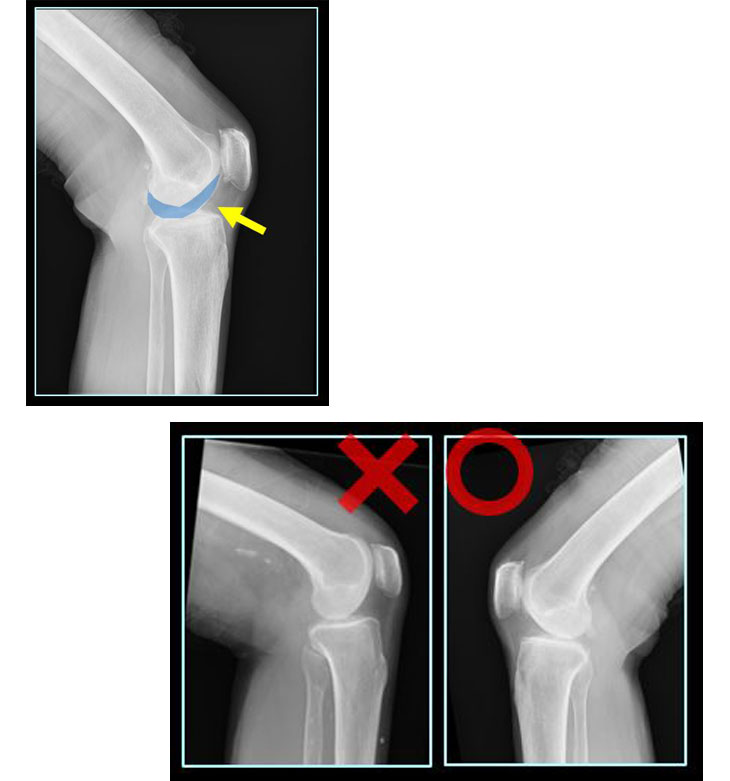

2. 画像診断ワークステーション CS-7

ポジショニング判定支援機能 <NEW>

『CS-7』コーナーでは新機能を紹介します。ポジショニング判定支援機能は、ポジショニングの精度と撮影部位の左右間違いを判定することで、不要な再撮影削減と再撮影判断時間の短縮、左右間違い画像の送信防止など、医療安全と業務効率化に貢献します。また入射表面線量算出機能では、画像と撮影条件から患者の体厚を推定。体厚情報を用いた入射表面線量の算出と、体型別の線量管理を可能にします。

『FINO.XManage』は各種モダリティやPACSから線量情報を取得し、画像と共に管理可能なシステムです。画質を担保しながら医療被ばくの最適化に貢献します。さらに一般撮影の多様なデータを可視化し、分析可能なマネジメント機能『RADInsight』を搭載。再撮影の管理に加え、撮影技術の教育支援ツールも備えています。『FINO.XManage』は、医療被ばくの最適化に向けてお客様をサポートします。